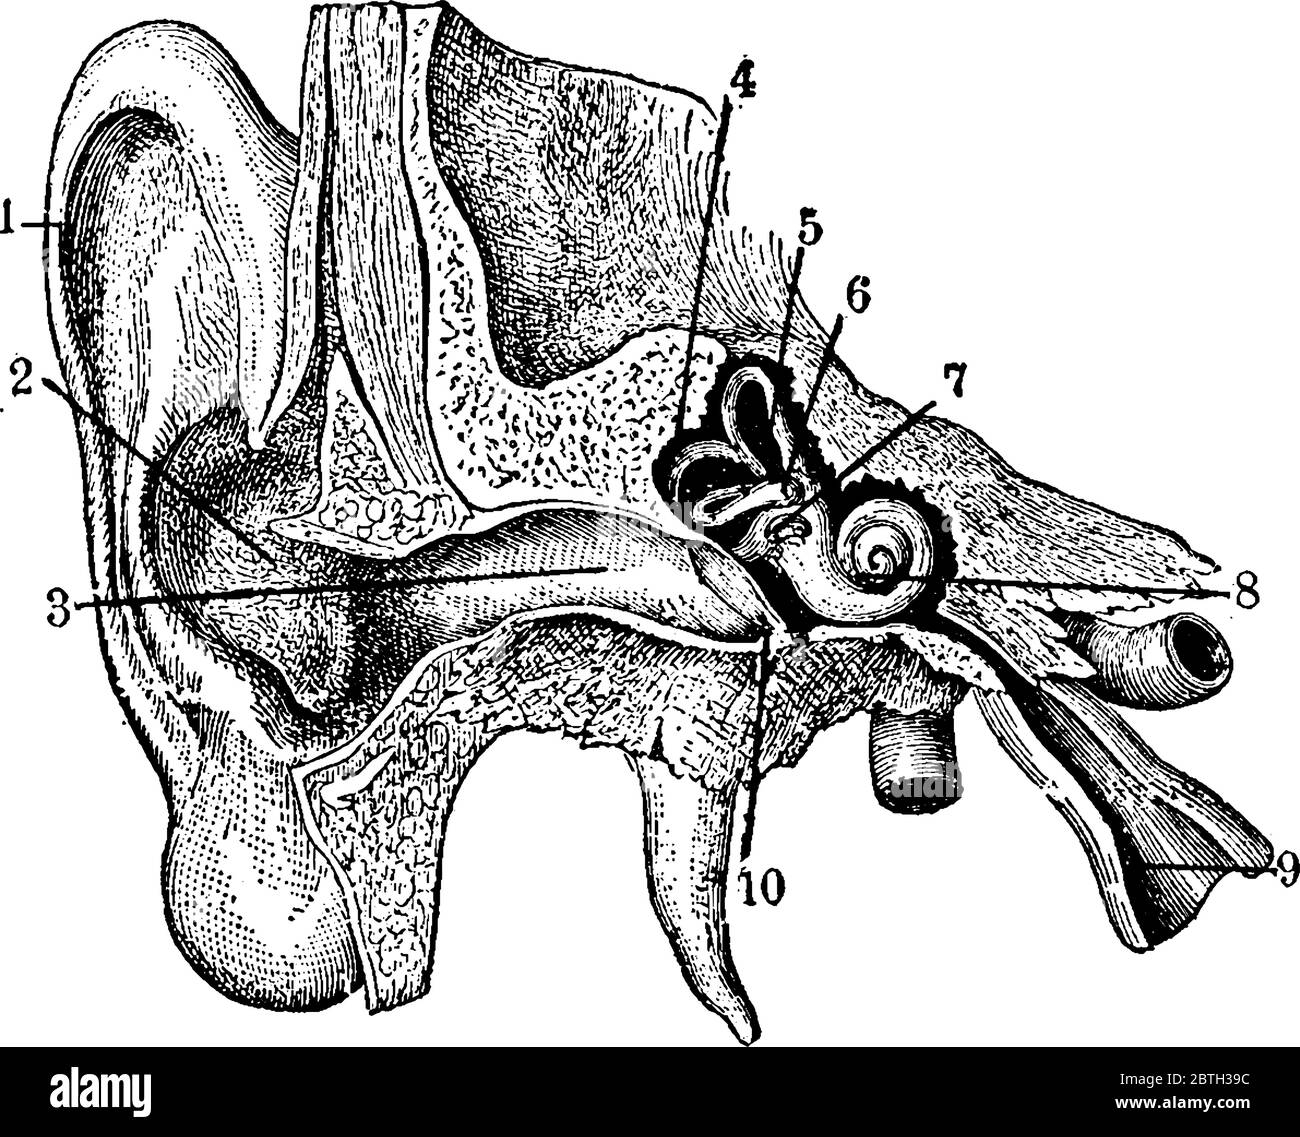

Schéma illustrant l'anatomie de l'oreille externe et interne, dessin de ligne vintage ou illustration de gravure. Illustration de Vecteurhttps://www.alamyimages.fr/image-license-details/?v=1https://www.alamyimages.fr/schema-illustrant-l-anatomie-de-l-oreille-externe-et-interne-dessin-de-ligne-vintage-ou-illustration-de-gravure-image359334904.html

Schéma illustrant l'anatomie de l'oreille externe et interne, dessin de ligne vintage ou illustration de gravure. Illustration de Vecteurhttps://www.alamyimages.fr/image-license-details/?v=1https://www.alamyimages.fr/schema-illustrant-l-anatomie-de-l-oreille-externe-et-interne-dessin-de-ligne-vintage-ou-illustration-de-gravure-image359334904.htmlRF2BTH39C–Schéma illustrant l'anatomie de l'oreille externe et interne, dessin de ligne vintage ou illustration de gravure.